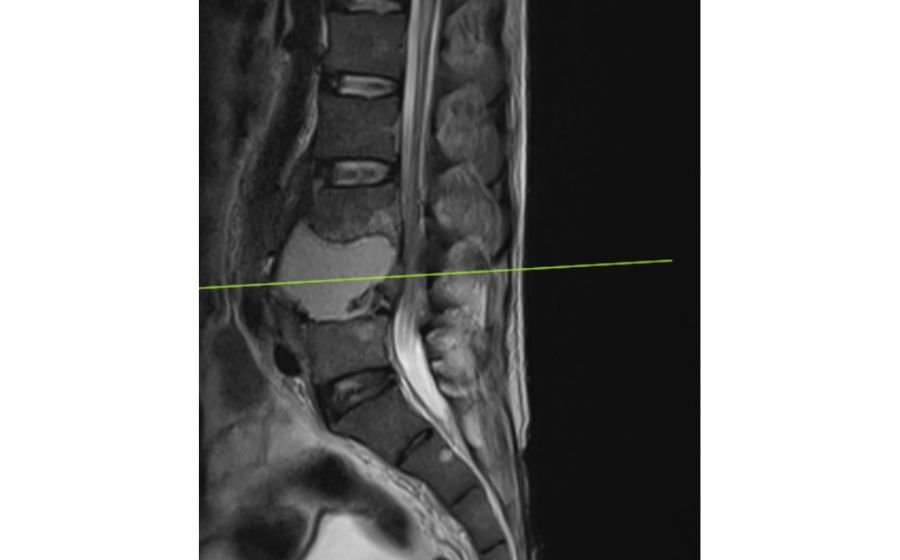

Osteoporotic Fractures

Osteoporotic fractures occur when weakened bones—most commonly in the spine due to osteoporosis—collapse even with minimal strain or a simple fall. These fractures can cause sudden back pain, loss of height, and forward bending of the spine. Diagnosis is made through X-rays, MRI, and bone density testing to assess bone strength. Treatment includes pain control, bracing, and medications to improve bone health. Minimally invasive procedures such as vertebroplasty or kyphoplasty can provide rapid pain relief and prevent further collapse. The focus is on restoring comfort, mobility, and long-term bone protection.